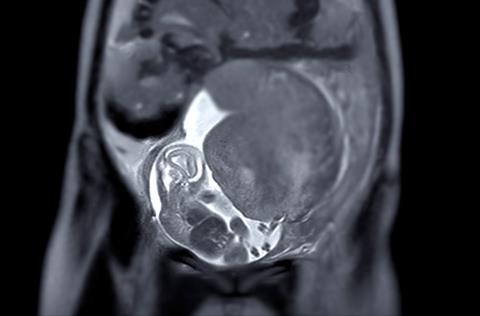

A new mouse study from the University of Illinois Urbana-Champaign, published in Brain Behavior and Immunity, has discovered that severe influenza in pregnancy compromises placental and brain barriers in mice – allowing harmful molecules to reach the foetal brain. Due to the use of live viral exposure, the findings may translate to humans, highlighting the importance of vaccination.

Previous studies showed that small molecules could pass through the placenta when pregnant mice were exposed to inactivated viruses. This study is the first to show placental breakdown with live influenza. It also demonstrated that fibrinogen – a molecule associated with neuroinflammatory conditions such as multiple sclerosis and Alzheimer’s disease – can infiltrate foetal brains.

Pregnant mice were infected with live influenza A virus at moderate and severe doses – simulating typical and extreme cases of human seasonal flu. At a stage equal to the end of the first trimester, the team injected the mice with fluorescent tracers of different molecular weights to track where these molecules accumulated in foetal tissues.

“We found that the largest tracers, which should not be able to get into the brain with an intact blood-brain barrier, accumulated in the foetal brain when the mums had severe influenza infections,” said the study’s first author, Rafael Gonzalez-Rincon, doctoral candidate in the Neuroscience Program in the College of Liberal Arts and Sciences at U. of I. “Tracers of all sizes also accumulated in the foetal liver and in the placenta for the severe infection group.”

The researchers found fibrinogen accumulation in the foetal brains of mice with severe influenza. Both fibrinogen and large tracer molecules concentrated in the subventricular zone and choroid plexus, suggesting vulnerability of the blood-brain and blood-cerebrospinal fluid barriers during prenatal infection.